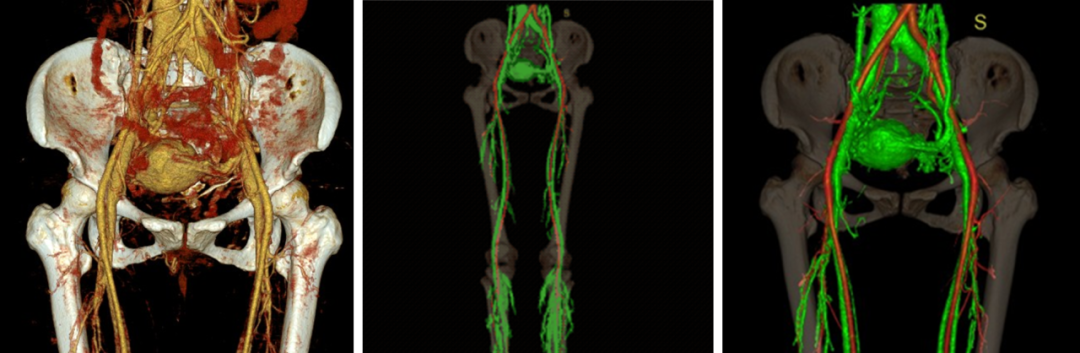

CTV / MRV:提供详细解剖结构,指导手术规划。

Sandwich技术优化-节约版

GLUBRAN替代Onxy;

双股静脉入路:可调弯鞘解决反流支;

示例(D-IIV)

示例(LOV+LCV)